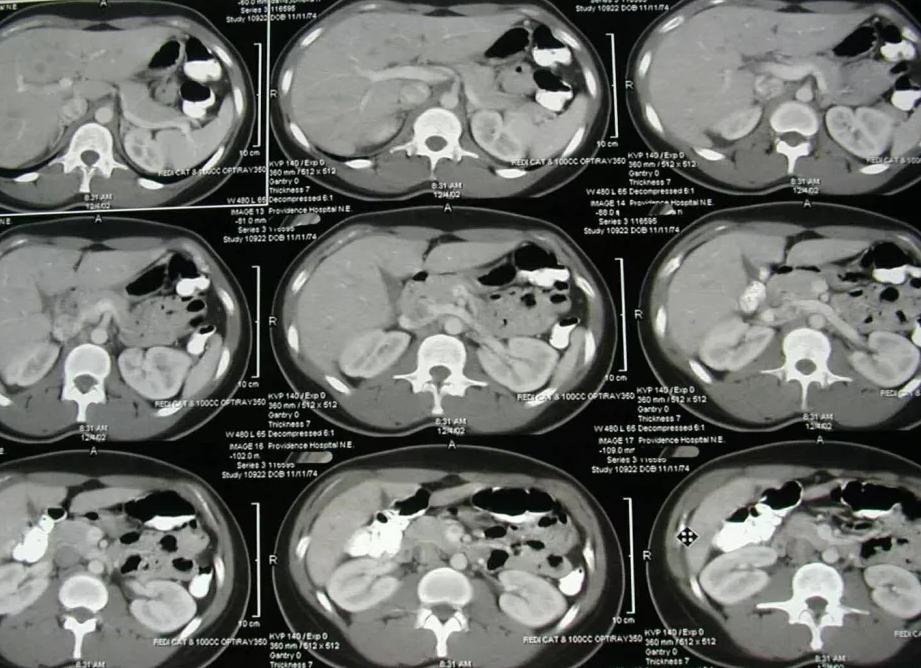

Что может показать компьютерная томография органов брюшной полости

При КТ забрюшинного пространства и органов брюшины визуализируются перечисленные выше органы, а также сосуды и абдоминальные лимфатические узлы. Процедура проводится для получения снимков в трехмерном формате и в высоком разрешении. С точки зрения диагностики очень важно, что КТ внутренних органов позволяет получить послойное изображение органа благодаря тому, что снимки делаются с разных углов.

Что показывает компьютерная томография? Сделать КТ рекомендуется дл обнаружения патологических процессов, в том числе воспалений и появления новообразований. Этот метод позволяет увидеть:

- Наличие инородных тел.

- Появление абсцессов.

- Формирование новообразований.

- Кровоизлияния.

- Сосудистые нарушения.

- Изменения в работе лимфатических узлов.

Кроме того, к КТ органов брюшной полости и забрюшинного пространства прибегают при подготовке к операциям и принятии решения об их целесообразности. Это показанный метод при нарушениях мочевыделительной функции и пищеварения, если прочие способы диагностики не принесли результата. КТ забрюшинного пространства и брюшины выполняется после травм и после операций, когда нужно проверить их результативность.